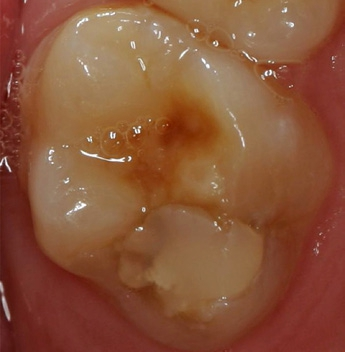

- MIH-Schmelz frakturiert oft; zusammen mit einer unzureichenden Mundhygiene ergeben sich Plaqueretentionsstellen. Gerade MIH-Molaren weisen daher oft zusätzlich auch kariöse Läsionen auf. Die genannte Empfindlichkeit, der oft beobachtete Zusammenbruch großer Schmelzareale und die Kariesanfälligkeit führen gerade für MIH-Molaren zu einer dramatisch erhöhten Behandlungsnotwendigkeit [4,24,25,28,30,36]. Da diese Behandlungen dann oftmals schmerzhaft sind, weisen Kinder mit MIH statistisch gesehen deutlich mehr Zahnarztphobien auf. Deswegen ist eine wirksame Schmerzkontrolle von wesentlicher Bedeutung, wobei Aspekte wie Verhaltensformung, eine adäquate Anästhesietechnik und Prämedikation (Analgetikum), Lachgas-Sedierung und im Extremfall eine Narkose angewandt werden können [25,57].

- MIH wird oftmals nicht frühzeitig diagnostiziert und mit kariösen Läsionen verwechselt (gerade im Molarenbereich). Das Ergebnis ist eine (teilweise verfrühte) invasive Therapie dieser Zähne mithilfe restaurativer Konzepte, die für kariöse Defekte (Fissurenkaries, approximale Karies) ausgelegt sind, in MIH-Zähnen jedoch oft nicht zum Erfolg führen. Die resultierenden Restaurationen sind gekennzeichnet durch ihre untypische Ausdehnung (Höckerersatz, Ersatz ganzer oraler oder bukkaler Flanken). Die Diagnose „MIH“ kann mitunter nur auf der Basis dieser Karies-untypischen Ausdehnung gestellt werden (Abb. 2). Eine internationale Arbeitsgruppe hat Ende 2016 einen MIH-Behandlungsbedarfsindex (MIH-TNI) entwickelt, der die wichtigsten klinischen Probleme (Ausmaß der Zahnhartsubstanzzerstörung und Hypersensibilität) bei Patienten mit MIH berücksichtigt. Basierend auf dem individuellen Kariesrisiko des Patienten in Kombination mit dem MIH-TNI kann der Behandlungsbedarf bestimmt werden [54,55].